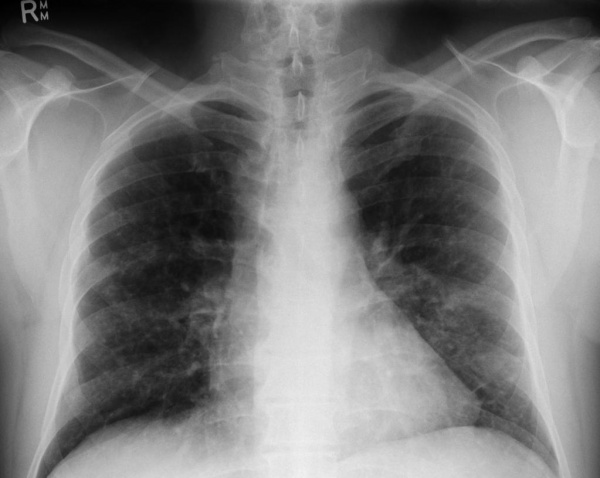

(Слева) На краниограмме в боковой проекции у ребенка с хроническим диссеминированным ЛКГ визуализируются типичные мелкие «выштампованные» просветления.

(Справа) На корональной КТ в костном окне у женщины 28 лет в ветви нижней челюсти справа визуализируются мелкие эозинофильные гранулемы с четкими контурами. Обратите внимание на истончение (но не перфорацию) щечной кортикальной пластинки. Патологический очаг, лежащий под нижнечелюстным каналом, распространяется в сторону щечной кортикальной пластинки.

(Слева) Рисунок в боковой проекции: множественные литические очаги костей черепа, которые можно наблюдать при лантергансоклеточном гистиоцитозе (ЛКГ). Очаги имеют скошенные края, указывающие на неравномерное поражение внутренней и наружной пластинок костей черепа.

(Справа) Рентгенография черепа в ПЗ проекции: типичная скошенность краев патологических очагов при классическом ЛКГ. Скошенность краев не является патогномоничной для ЛКГ, однако этот признак типичен и при наличии имеет высокую ценность. Кроме того, визуализируется секвестр, что является еще одним типичным признаком данного заболевания. (Слева) Рентгенография в косой проекции, выполненная тангенциально выпуклости на черепе: визуализируется литический очаг, занимающий диплоитическое пространство и характеризующийся скошенным краем. Такая картина типична для ЛКГ, особенно у детей.

(Слева) На рентгенограмме черепа в прямой проекции визуализируются два очага ЛКГ в лобной кости: меньший (округлый с ровными контурами) и больший (неправильной формы). Для описания подобных поражений используется термин «географический череп». Очаги также определяются в нижней челюсти.

(Справа) На рентгенограмме в косой боковой проекции у этого же пациента определяется «выскобленный» очаг вокруг мезиального корня формирующегося 1-го моляра. Пациент страдает хроническим диссеминированным ЛКГ, клинически проявляющимся экзофтальмом.